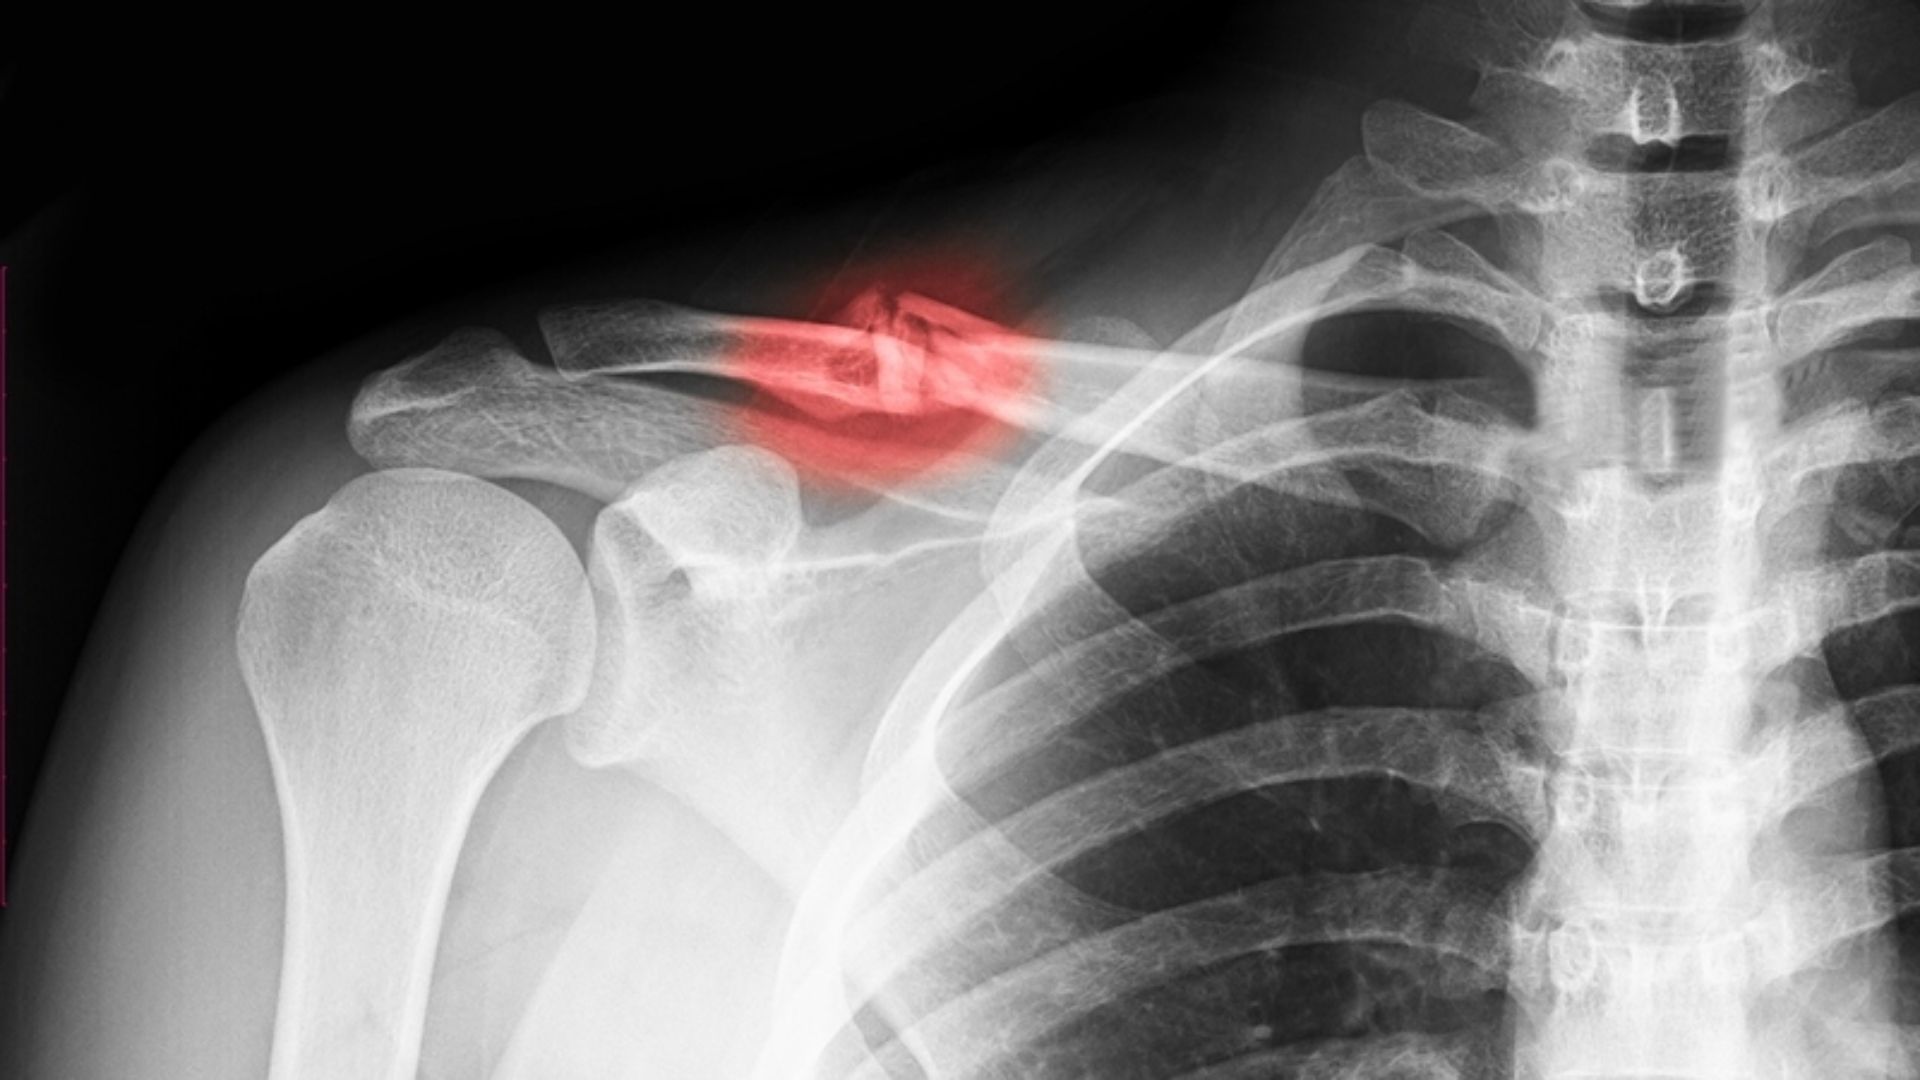

Gãy xương đòn

Gãy xương đòn là loại gãy xương phổ biến, thường xảy ra do té ngã chống tay, tai nạn giao thông hoặc chấn thương thể thao như bóng đá, xe đạp. Tình trạng này hay gặp ở trẻ em và thanh thiếu niên vì xương đang phát triển với các biểu hiện như đau dữ dội, sưng nề, biến dạng vùng vai và hạn chế vận động, thường cần bất động hoặc phẫu thuật nếu lệch nhiều.